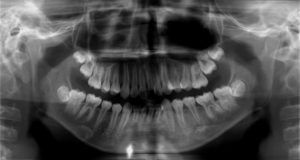

10歳くらいのお子さんがいらっしゃる方はお子さんの歯をよく見てみて、歯の噛みあう場所の面のところに、ツノのようなものがあったら、要注意です!

何故かというと、 中心結節の中には神経の管があり、破折すると、神経が出て、シミや噛んだ時の痛み、歯茎の腫れなどが起こることがあります。

しかし、虫歯ではないので初期の場合、レントゲンでは悪くなった状態がわからないこともあります。歯医者でも知覚過敏や歯ぎしりなどとの違いに診断を下すのが難しい場合があります。

この場合は歯の根が感染していたため通常の治療を行いましたが、年齢も若く根が出来上がっていませんでした。

ある論文*1 によると 、中心結節に関しては接着性レジン(プラスティック)によって割れないように予防することでほとんどが予防できるという発表もあります。